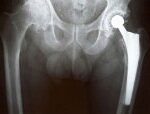

Τα μεταλλικά εμφυτεύματα στο ισχίο χαλάνε εύκολα και κρύβουν κινδύνους, λένε τώρα οι επιστήμονες.

Τα αμιγώς μεταλλικά εμφυτεύματα που τοποθετούνται στο ισχίο, παύουν να λειτουργούν σωστά σε πολύ μεγαλύτερο ποσοστό σε σχέση με άλλες εναλλακτικές λύσεις, γι’ αυτό δεν πρέπει πλέον να τοποθετούνται στους ασθενείς. Σε αυτό το συμπέρασμα κατέληξαν βρετανοί επιστήμονες, που κρούουν τον κώδωνα του κινδύνου για τα πιθανά προβλήματα από τέτοια εμφυτεύματα, μια προειδοποίηση που έρχεται λίγο καιρό μετά το σκάνδαλο με τα επικίνδυνα εμφυτεύματα στήθους.

Τα εμφυτεύματα του ισχίου θεωρούνται μια από τις μεγάλες επιτυχίες της σύγχρονης ιατρικής, καθώς αποκαθιστούν τη δυνατότητα κίνησης του ασθενούς και μειώνουν τον πόνο. Παρόλα αυτά, όπως δείχνει η νέα μελέτη, ο κίνδυνος αποτυχίας δεν είναι καθόλου αμελητέος, ιδίως για τα αμιγώς μεταλλικά εμφυτεύματα. Το πρόβλημα εντοπίζεται κυρίως στις μεταλλικές αρθρώσεις, οι οποίες σιγά-σιγά είτε φθείρονται με τη χρήση, είτε βγαίνουν από τη σωστή θέση τους.